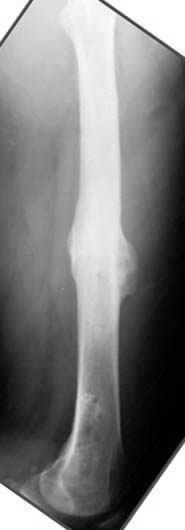

Несколько снимков из моей коллекции, чтобы разьяснить, почему мы до сих пор делаем различные варианты остеотомии.

На рисунке N1 предоперационный план лечения ложного сустава шейки бедра- линия ложного сустава, угол и направление введения импланта, клиновидная остеотомия в градусах и миллиметрах, второй снимок после коррекции, расчет, на сколько удлиняется конечность и размеры импланта;

N3 рисунок окончательный снимок, после операции моя рентгенограмма должен выглядеть примерно как эта картина. На N4 снимке клин перед удалением; N5 послеоперации 3 нед.; N6 окончательная рентгенограмма.

(доложен в Ст. Петербурге 2003 и в Москве 2004)

Отправитель: Djoldas Kuldjanov 23 Ноябрь 2004, 18:21

пластическая модель; и коррекция бедра аппаратом Илизарова.

Имею другие снимки тоже, получится как отчет о моей работе.